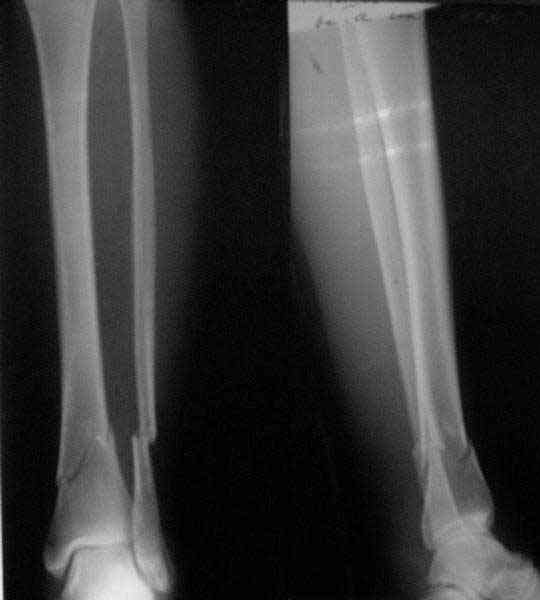

A typical case is attached, also an image with intra-op reduction obtained by a small wire distractor, in the moment of insertion a Poller wire in AP direction. Fixation by a SIGN nail. Despite the fibula was not fixed healing was obtained with the unchanged alignment.

Very interesting application, but is the final position in a little distal varus with some fibula

distraction? Would that have been eliminated by fibula plating?

At least both the ankle mortise and tibial alignment look acceptable, don't they?

I am just trying to illustrate that prevention of 1)tibial valgus and 2)loss of reduction can be provided without fibular plating. Small changes of conventional nailing techniques allow to maintain reduction of the tibia reliably without adjunctive fibular stabilization.